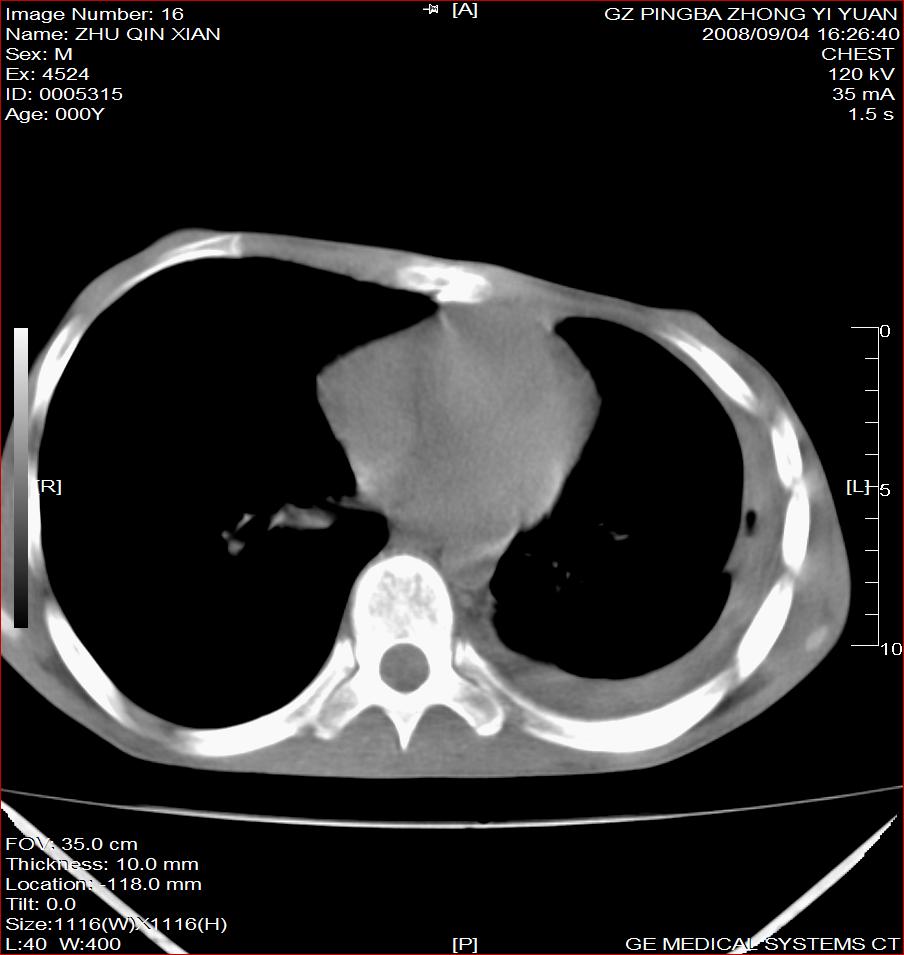

以下是引用随光逐影在2008-9-4 20:05:00的发言:[br]1)考虑两肺结核。2)左侧胸膜炎(胸膜肥厚、粘连,胸腔积液)。3)左侧局限性气胸。

以下是引用子十在2008-9-4 19:34:00的发言:[br]左上肺结核并空洞及双肺播散。节段性肺不张、胸腔积液、胸膜肥厚粘连。[br]